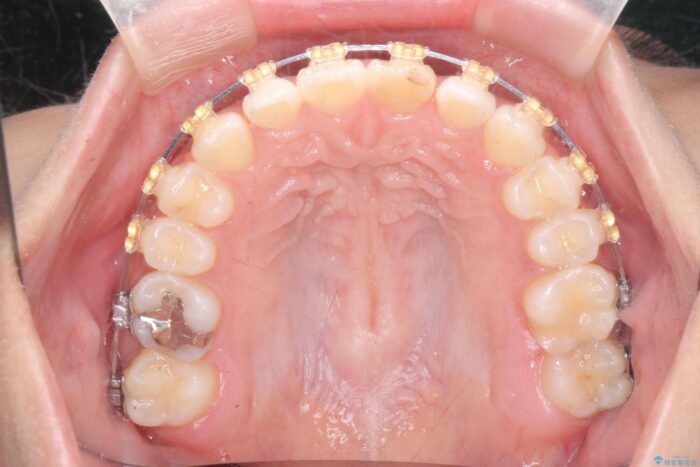

仕上がりにこだわりたいと、装置はマウスピースではなくワイヤーを希望されました。

マルチブラケットを用いた非抜歯のワイヤー矯正で噛み合わせと歯並びを改善していきます。

1年で歯並び、嚙み合わせともにしっかりと改善されました。

患者様にも、非常に噛みやすくなったと喜んでいただくことができました。